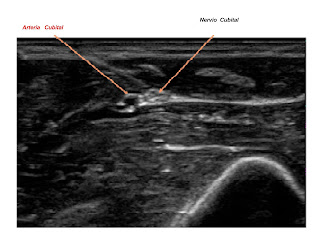

En la muñeca, el nervio cubital pasa lateral al hueso pisiforme y medial al hueso ganchoso en una zona conocida como el canal de Guyon. La arteria cubital esta antero lateral al nervio a este nivel da inervación motora al musculo cubital anterior y al flexor común profundo de los dedos, en la mano inerva todos los músculos que están situados por debajo y por dentro del tendón flexor largo del pulgar y no emite ramas sensitivas del antebrazo, suele inervar la piel del dedo meñique y la mitad interna de la mano y del dedo anular